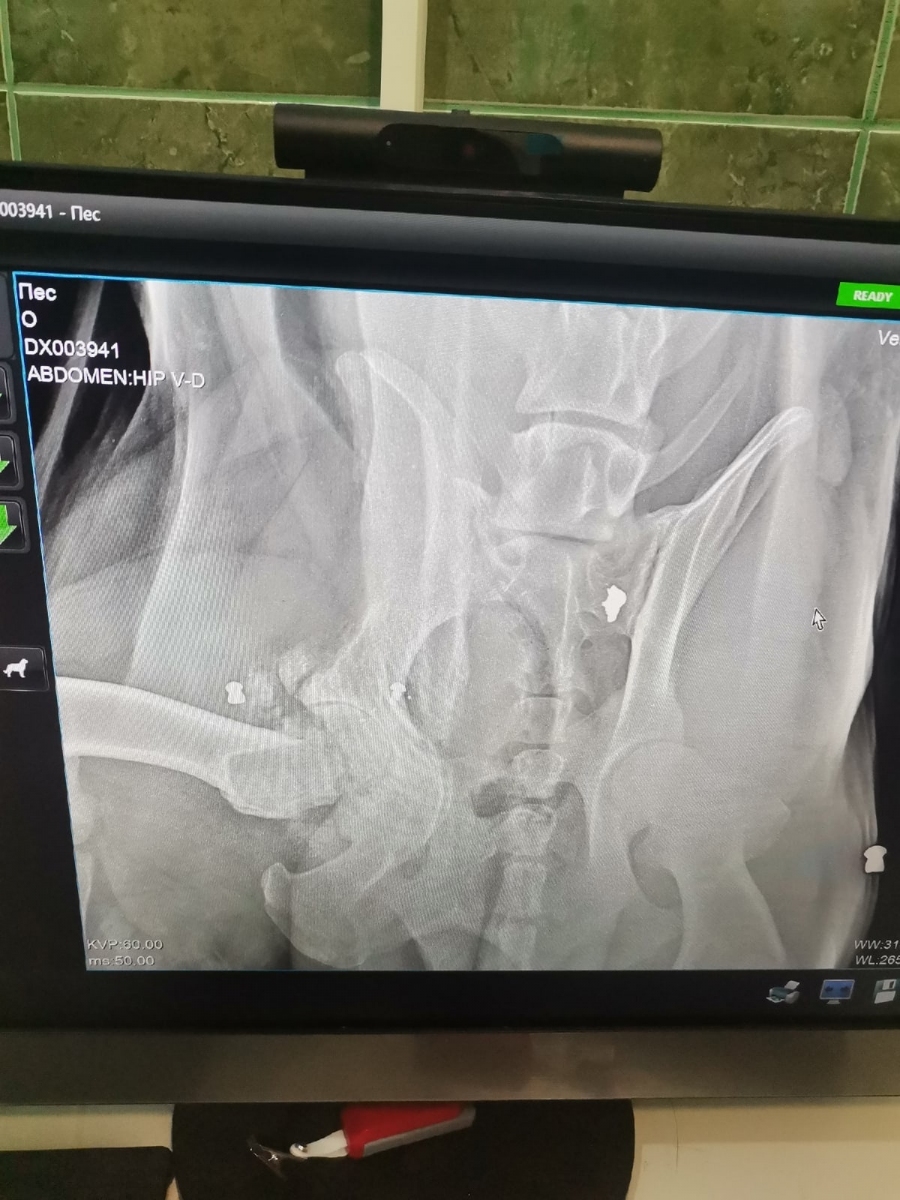

Рядом с местом, где лежала собака, были видны следы от трёх других мест, где выживало животное: стало понятно, что там беззащитный пёс находился не первый день. Пострадавшую собаку свозили в клинику: оказалось, что у неё есть переломы и она вся напичкана свинцом: кто-то избил животное, расстрелял и выбросил умирать.

Как окрепнет - можно вытащить пули, но не все: многие глубоко ушли, только те, что на поверхности. Лекарства, приём и рентген я оплатила сама, за следующий приём врач не взял ни рубля. Думаю, что надо подождать, чтобы Пират окреп, и сделать операцию - вытащить пули, - рассказала Елена Исаева.